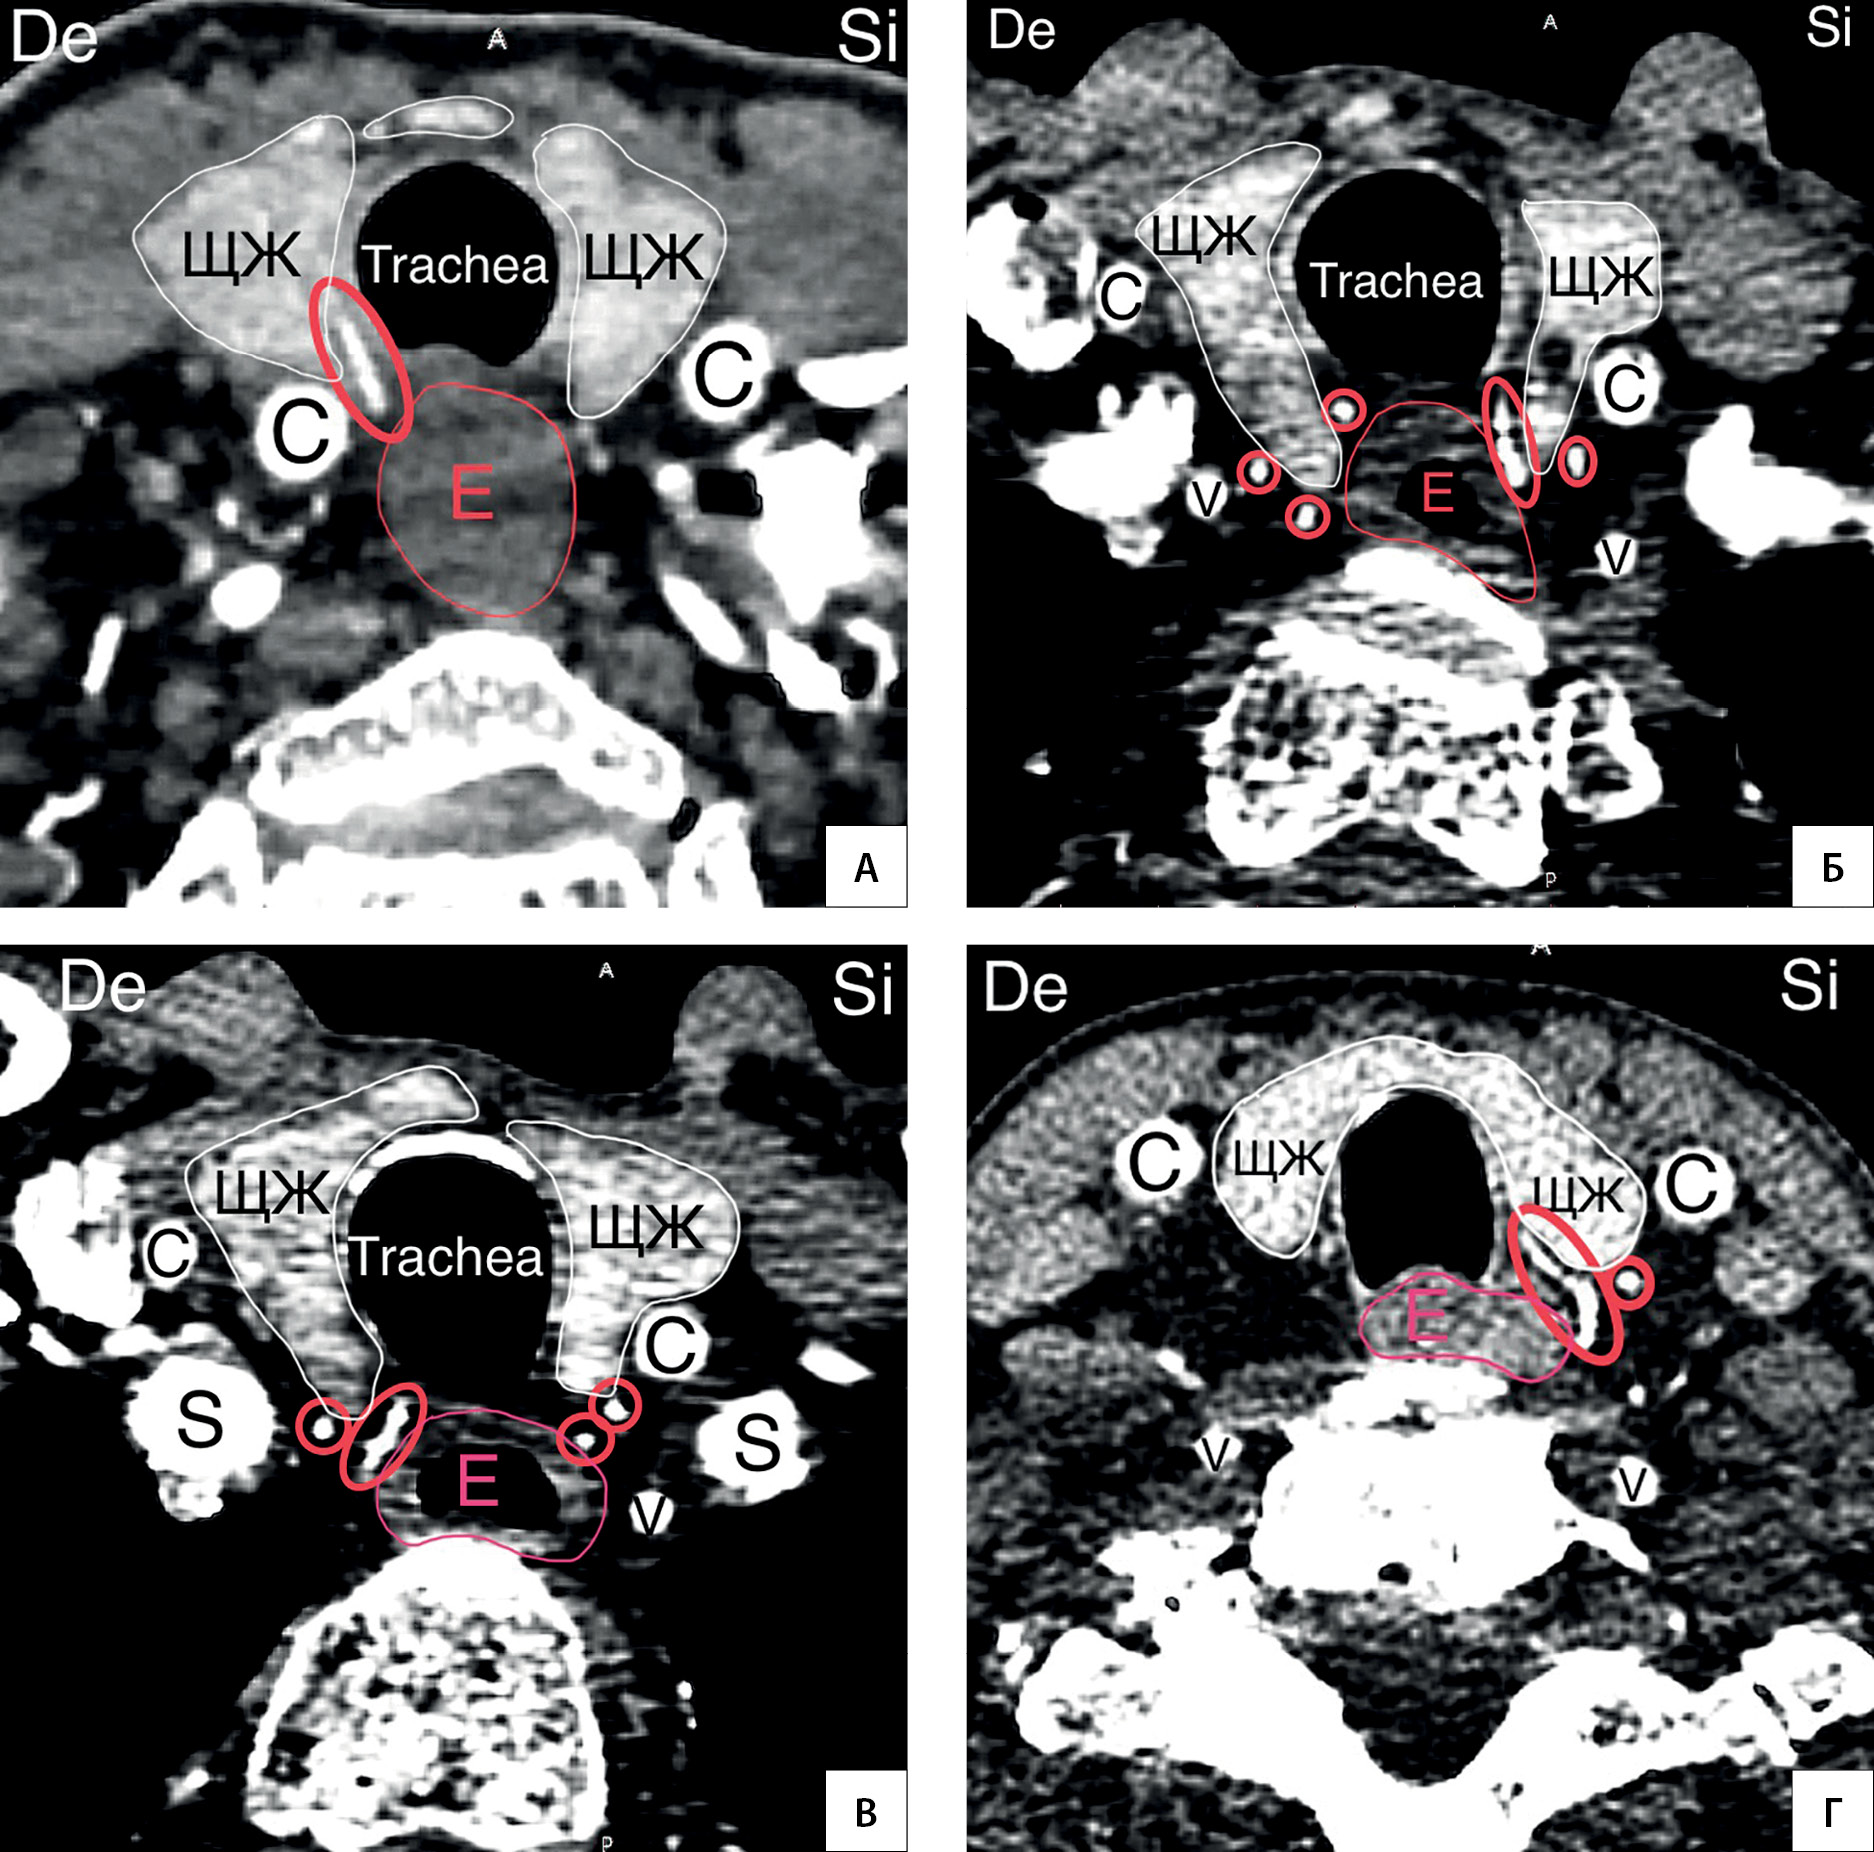

9. Рисунок 9. НЩА образует две ветви. А — КТ-ангиография (сагиттальный срез). Обе ветви направляются книзу (стрелки); Б — КТ-ангиография (сагиттальный срез). Восходящая и нисходящая ветви НЩА (стрелки); В — схематичный рисунок (вид спереди). Варианты расположения ветвей НЩА.

Тема

Тип Исследовательские инструменты

Посмотреть (542KB)

Метаданные ▾